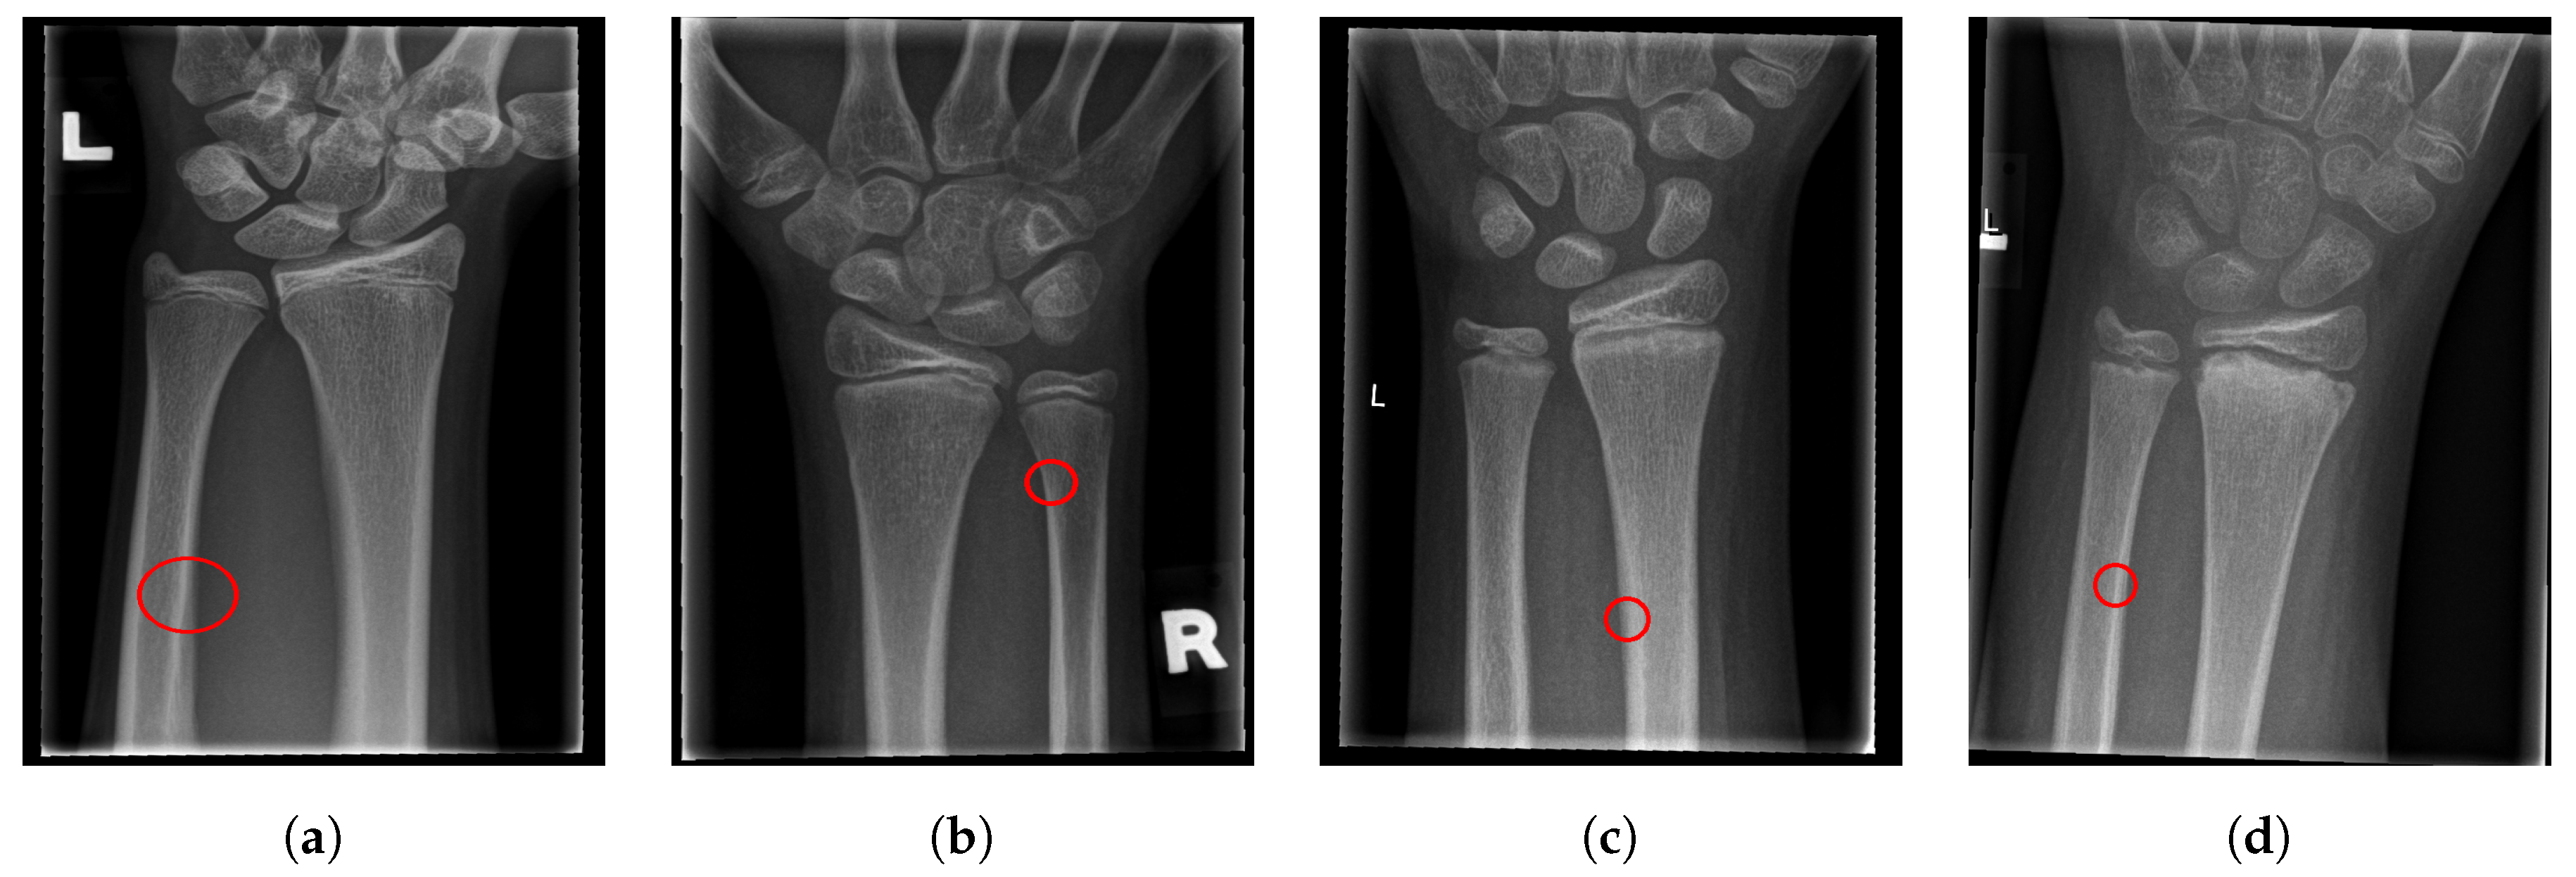

- False Negative (FN): The case when the image contains a fracture, but the algorithm failed to mark the image as fractured.